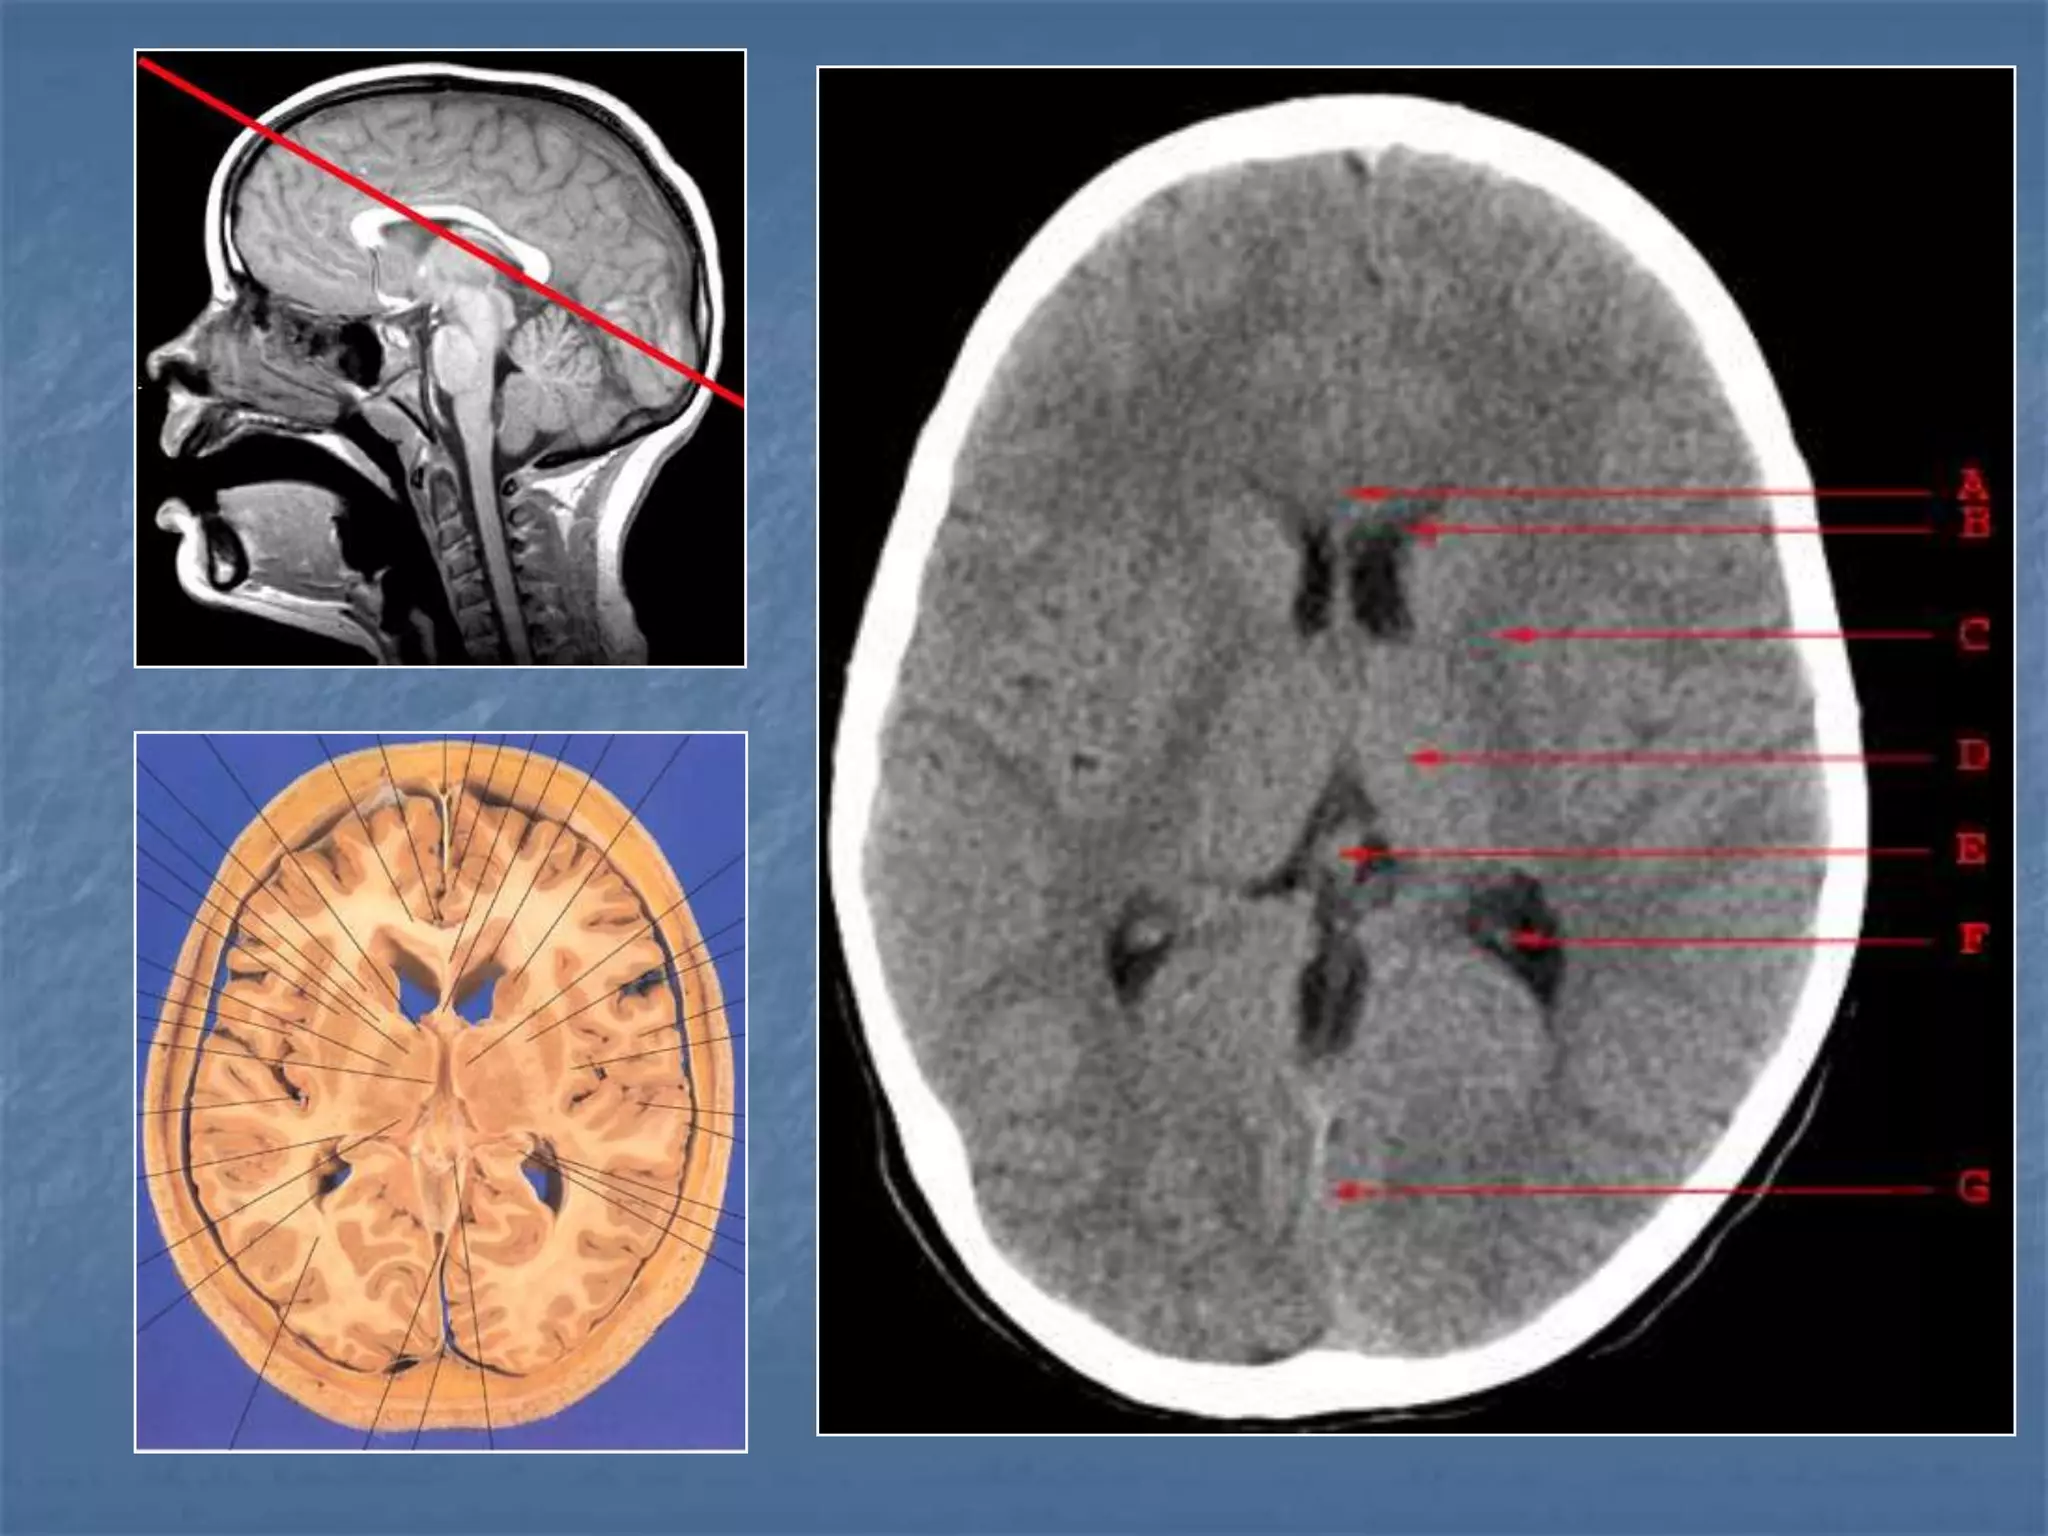

How the CT study is usually planned…

15-20 degree

angulation to

canthomeatal line

to decrease

radiation to the

lens.

 Thinner sections

are studied

Hounsfield Units

AIR - - 1000

FAT - - 30 to -100

CSF - 0

GREY MATTER - 32 - 41

WHITE MATTER - 23 - 34

ACUTE BLOOD - 56 - 76

CALCIFICATION - 60 - 400

BONE - 1000